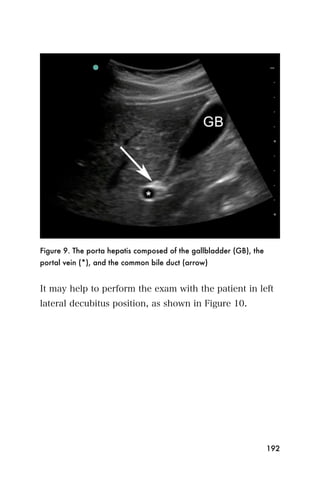

Figure 8. Mitral regurgitation show by blue color flow back into the left

We recommend that basic echocardiographers focus on

accurately. Fortunately, patients with moderate-to-severe

mitral regurgitation generally have dramatic murmurs on

physical examination.

other valvular or congenital heart disease.